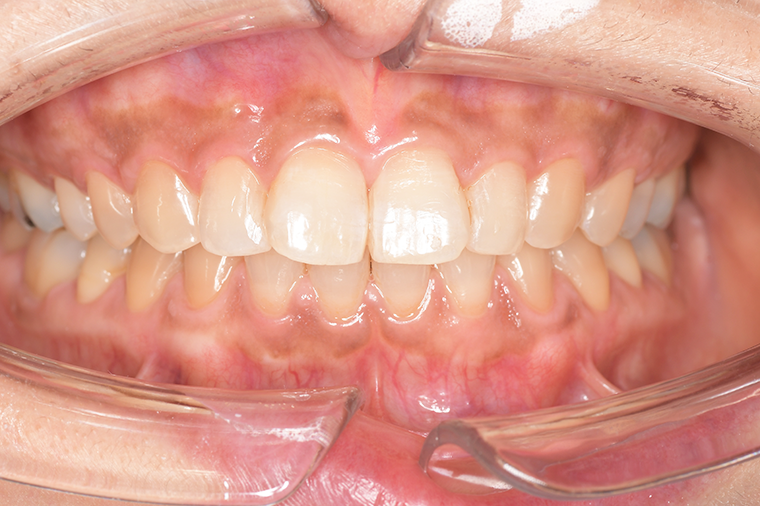

クリーニングの症例

現在の治療費と異なる場合がございます。最新の治療費は料金表をご確認ください。CASE 1

Before

After

基本情報

| 主訴 | 見た目をきれいにしたい |

| 治療期間 | 6ヶ月 |

| 治療費 | ジルコニアボンド(セラミックの被せもの)¥165,000×7(税込み) オフィスホワイトニング4回 ¥4,400×4(税込み) ホームホワイトニング¥11,000 |

| リスク・副作用 | かみ合わせがとても強い方の場合、稀に割れてしまうことがあります。 |

| 先生からの提案 | 上の前歯6本と右下の2番目の歯はセラミックの被せもので治療。 残りの下の前歯5本はプラスチックの材料で虫歯を治療し、 ホワイトニングをおこないました。白くなったご自身の歯の色に合わせてセラミックの 被せものを作成しています。 模型上で完成後をシュミレーションし、上の歯茎の位置をきれいに見えるように 揃えています。(外科処置はしていません) |